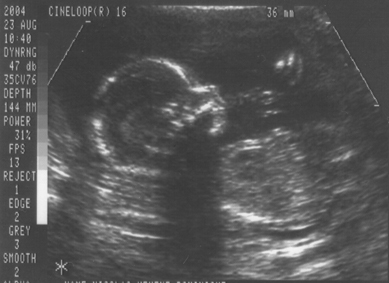

23. August 2004 (Ein Mädchen !)